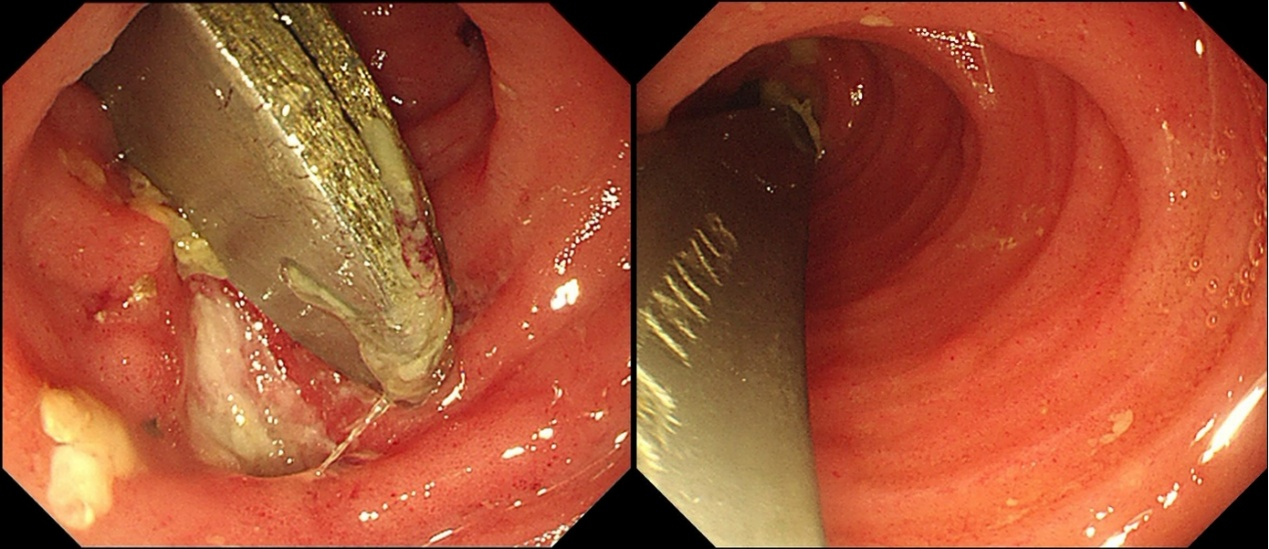

进镜后发现,勺子卡在回肠末端,因勺子长期卡在回肠末端的原因,周围的黏膜已形成溃疡,如不及时取出,则随时有穿孔的风险。勺子长度近12cm,卡在回肠末端,取出难度较大,但在消化内科王雷主任团队的密切配合下,最终成功在内镜下将异物完整取出,避免了外科手术。